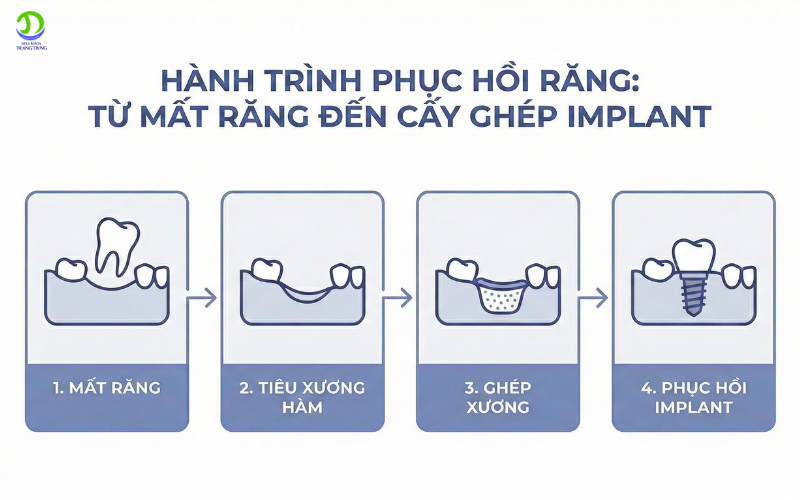

Hành trình phục hồi răng

Tiêu xương hàm và ghép xương được giải quyết hiệu quả nhờ kỹ thuật tái tạo xương hiện đại.

Ghép xương là quá trình:

-

Bổ sung vật liệu xương vào vùng bị tiêu

-

Kích thích xương mới phát triển

-

Tạo nền vững chắc cho Implant